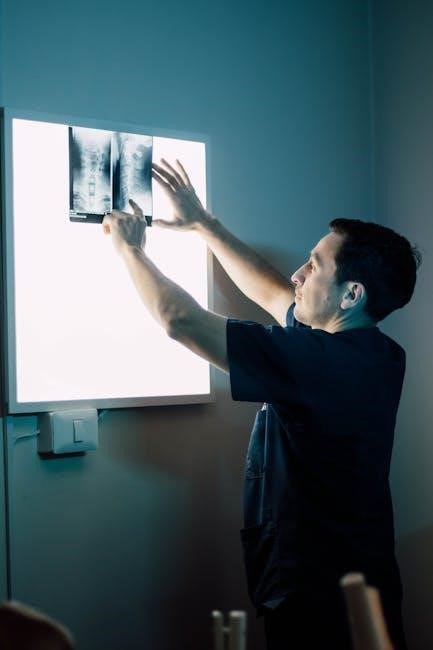

Diagnostic Imaging in Orthopedics

Diagnostic imaging in orthopedics includes X-rays‚ MRIs‚ and CT scans‚ essential for accurately diagnosing fractures‚ soft tissue injuries‚ and bone abnormalities.

5.1. X-rays and Their Terminology

X-rays are the most common imaging tool in orthopedics‚ providing clear visuals of bone structures. Terms like anteroposterior (AP) and lateral views describe the angles used. Weight-bearing X-rays assess joint alignment under load. Fracture terms include displacement and angulation. Degenerative changes like joint space narrowing are also visible. X-rays are essential for diagnosing fractures‚ monitoring healing‚ and detecting conditions like osteoporosis or bone spurs.

5.2. MRI and CT Scan Terminology

MRI and CT scans provide detailed imaging of bones and soft tissues. Terms like T1 and T2-weighted images describe MRI sequences. CT scans use slice thickness and reconstruction algorithms for clarity. MRI is ideal for assessing cartilage‚ ligaments‚ and discs‚ while CT scans excel in visualizing bone fractures and spinal issues. Both modalities use contrast agents to enhance image clarity‚ aiding in diagnoses like herniated discs or osteophytes without invading the body.